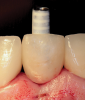

(12.) Placement of an appropriately sized implant into the osteotomy.

Figure 12

(13.) The appropriateness of the apical depth of the implant head was confirmed.

Figure 13